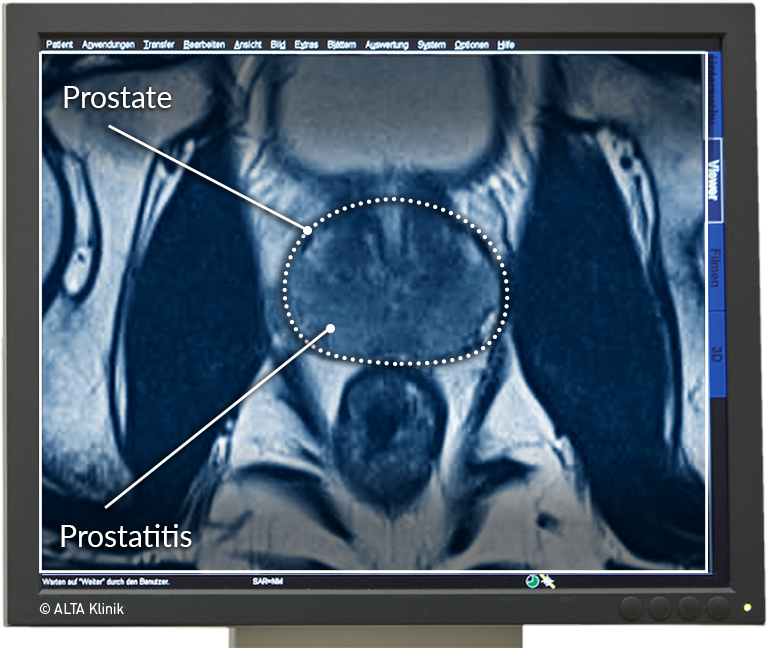

- gesunde Prostata

- Prostatitis